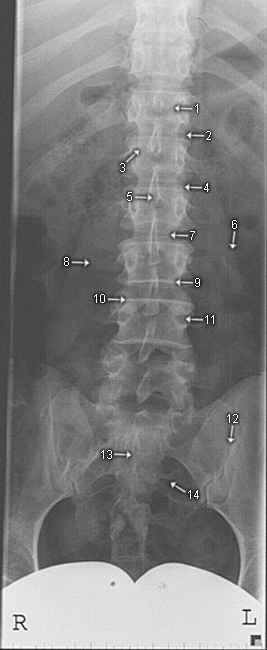

LWS a.p.

1. Corpus vertebrae

2. Processus articularis superior

3. Processus articularis inferior

4. Intervertebralgelenk

5. Processus spinosus

6. Psoasschatten

7. Zwischenwirbelraum

8. Processus transversus

9. Wirbelkörpergrundplatte

10. Wirbelkörperdeckplatte

11. Pediculus arcus vertebrae

12. Articulatio sacroiliaca

13. Os sacrum

14. Foramina sacralia